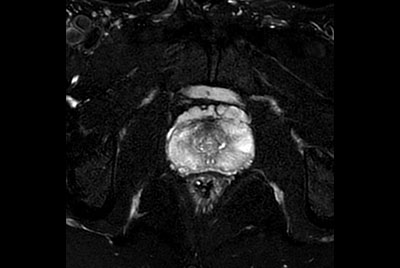

Compressed SENSE Prostate imaging